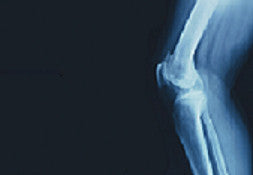

Tendons and Ligaments are notoriously slow/poor at healing. When they get injured, the body does what it can to repair them. However, because of their poor blood supply, they often heal incompletely.

The most common injuries are strains and sprains, as well as tears. There are many ways to heal from these injuries. However, if healing is incomplete, these once strong and tight tissues become lax, weak and painful.

The good news is that these injuries that don’t respond to conservative treatment (rest, ice, physical therapies, etc) can be repaired with a natural technique called prolotherapy.

Prolotherapy involves injecting a solution into the damaged area. The solution works to directly repair and regenerate healthy tissue. Once repaired, tendons and ligaments are stronger and quite often the person is able to return pain-free to their sport.